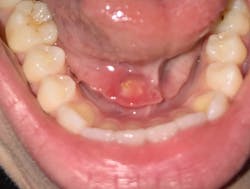

A 19-year-old female presented to our clinic with a complaint of swelling and pain from the lower right mandibular area, as well as sharp pain below her tongue. Examination revealed a swollen right submandibular gland and significantly enlarged Wharton’s duct papillae, with an area approximately 4 mm wide of calculi seen within the duct (figures 1 and 2).